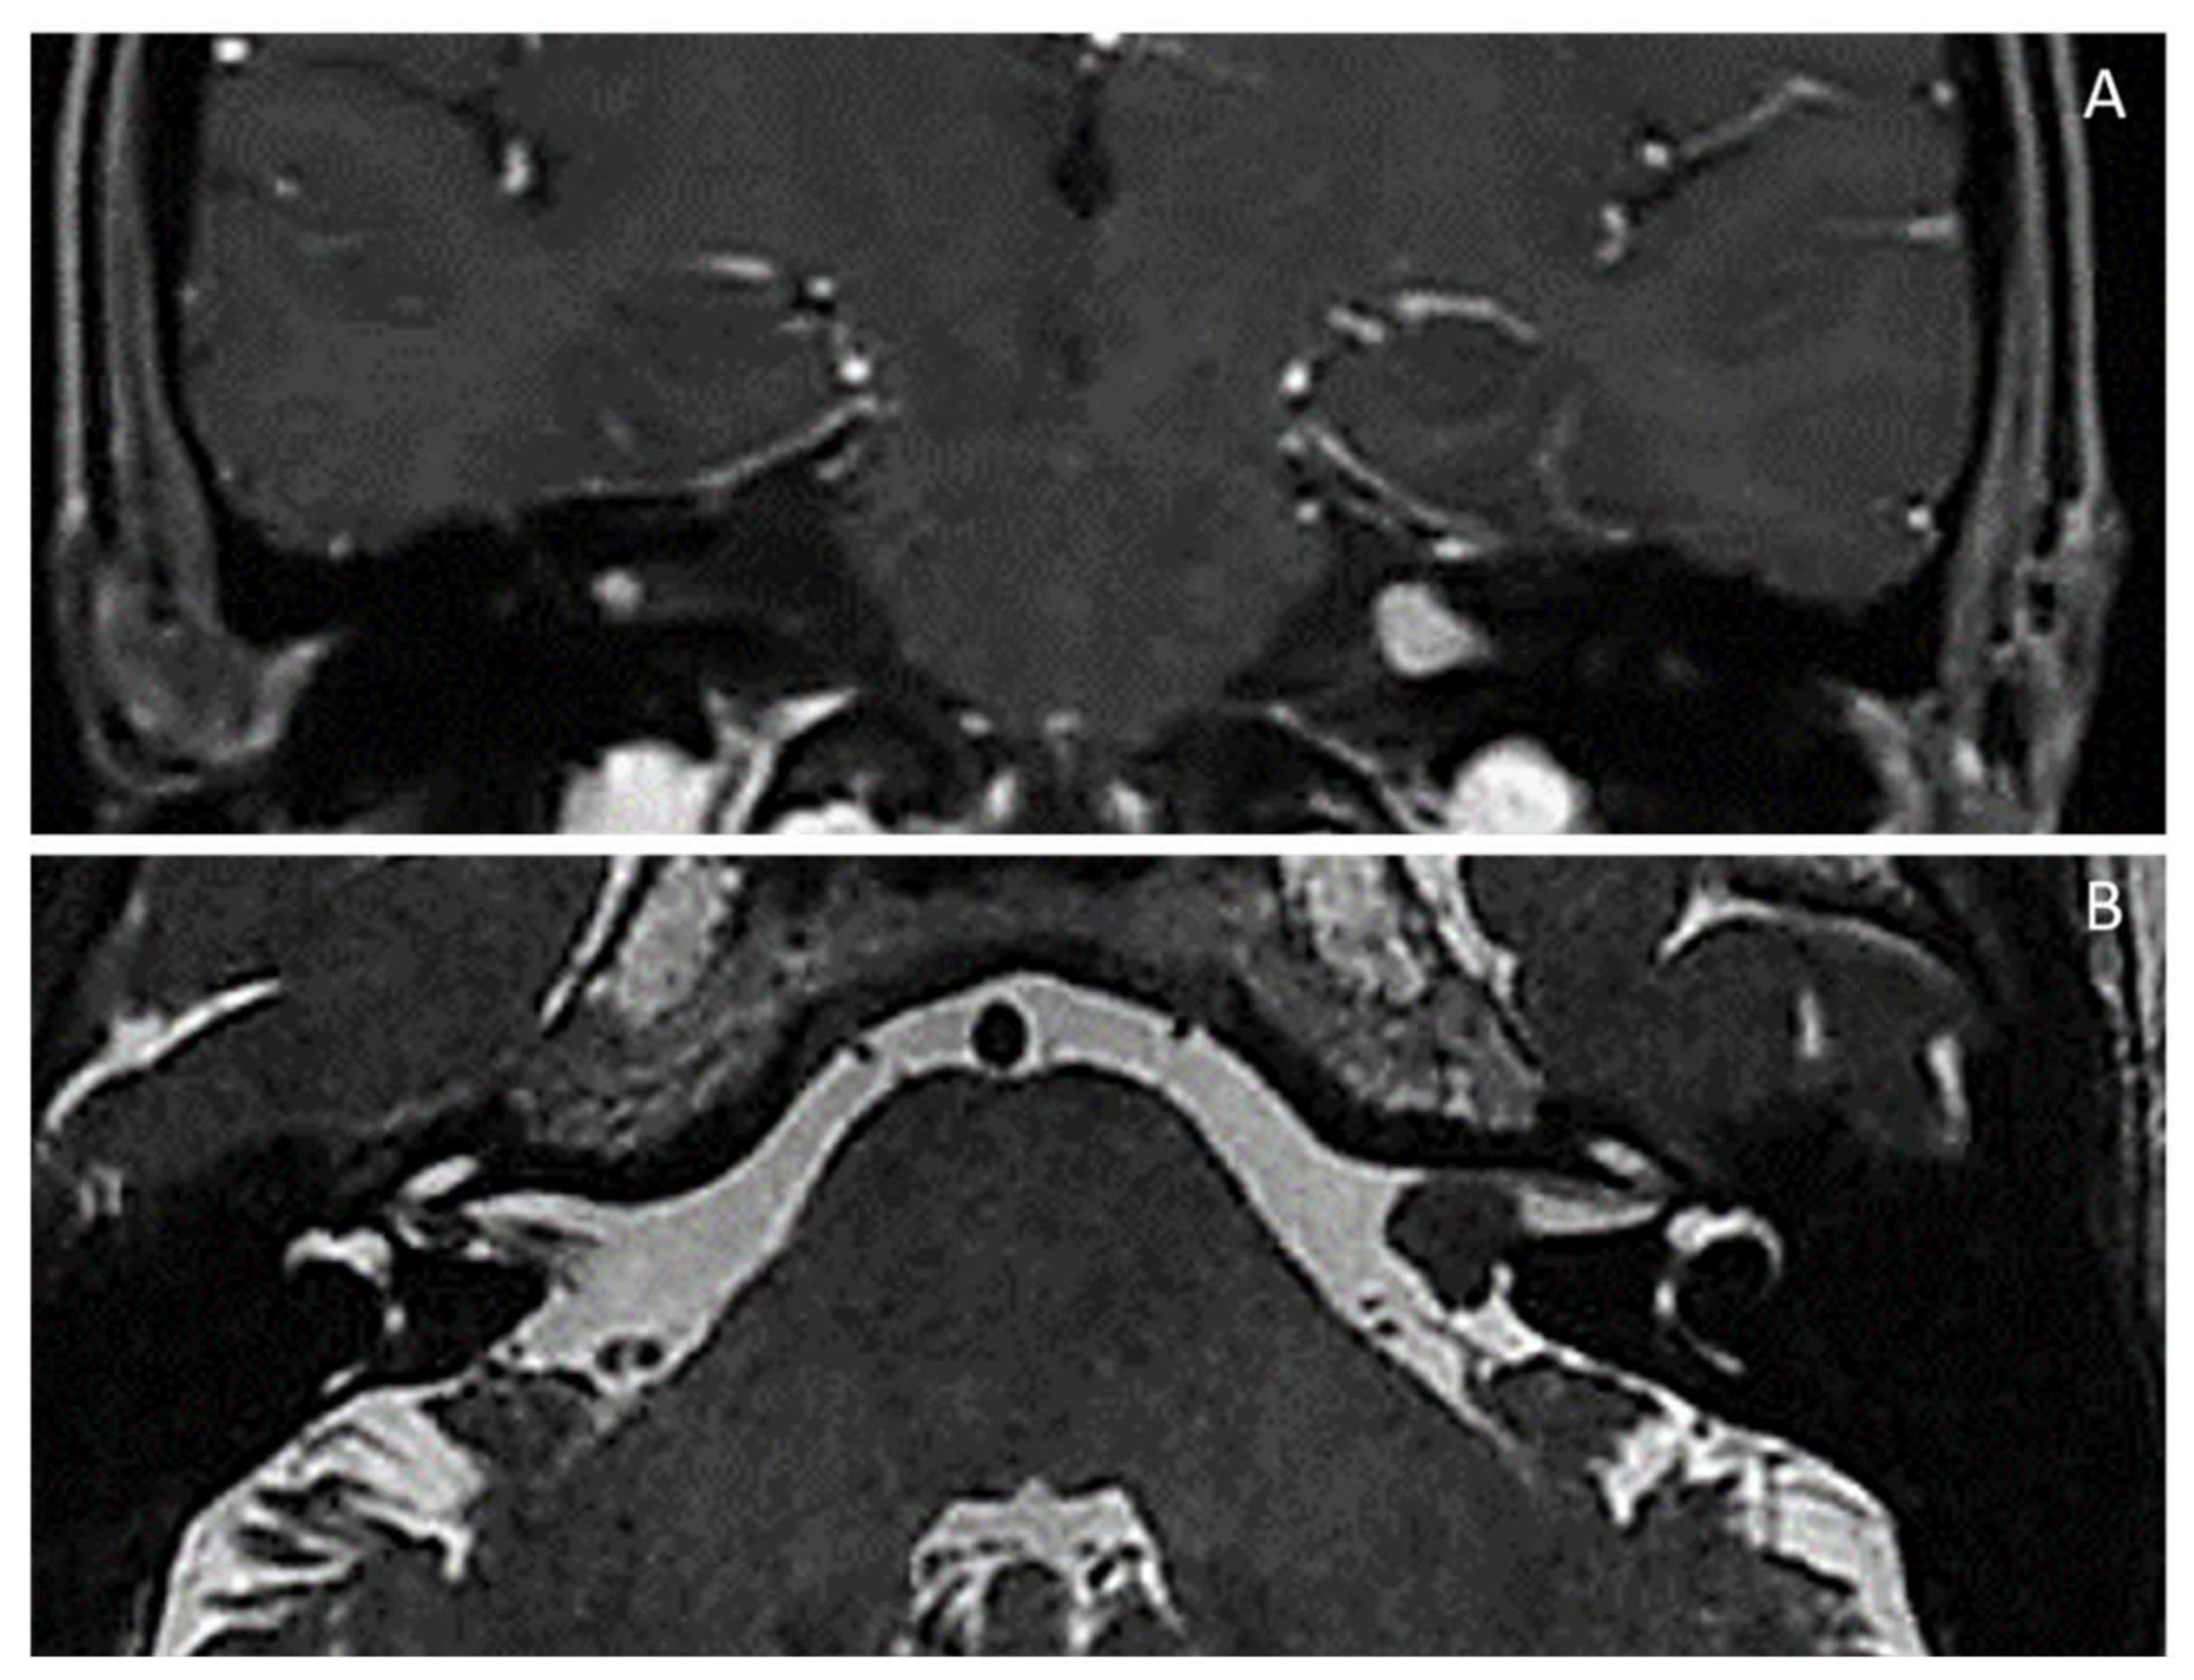

NF2-related schwannomatosis [NF2/MERLIN-schwannoma predisposing syndrome (NF2/MERLIN-SPS)] (Previously, neurofibromatosis type 2 or NF2) [MIM # 101000; ORPHA:637] Chromosome 22q12.2 (NF2/MERLIN moesin-ezrin-radixin-like gene): identical NF2 gene pathogenic variant in at least two anatomically distinctNF2related tumours (e.g., schwannoma, meningioma and/or ependymoma); NF2 gene variants in unaffected tissues (e.g., blood) and major/minor criteria (see below); Main features: (1) Gardner type (adulthood): Bilateral (or, sometimes, unilateral) VIII cranial nerve (vestibular) schwannoma(s) *; schwannomas of cranial nerves *; multiple meningiomas, ependymomas, schwannomas *; early-onset (posterior subcapsular or cortical) cataracts *; skin schwannomas (NF2 plaques) *; nodular schwannomas *; (2) Wishart (severe) type (childhood): prior to appearance of VIII nerve schwannomas * and/or nervous system tumours (meningiomas, ependymomas) *, non-VIII-cranial nerve schwannomas (e.g., mixed nerves, V, VII) *; early-onset (posterior subcapsular or cortical) cataract *; epiretinal membranes/hamartomas *; skin schwannomas (NF2 plaques) * diffused over body; brain cortical dysplasia; bone dysplasia; (3) Congenital type (neonatal/< 1 year): small bilateral VIII nerve schwannomas * stable for decade(s); optic nerve sheath meningioma(s) *; epiretinal membranes/hamartomas *; early-onset (posterior subcapsular or cortical) cataract *; skin schwannomas (NF2 plaques) * in atypical places (face, arms, legs) later disappearing; ependymomas *; spinal cord schwannomas and meningiomas *; brain cortical dysplasia; |

Mosaic (segmental)NF2-related schwannomatosis [Mosaic NF2/MERLIN-schwannoma predisposing syndrome] (Mosaic NF2/MERLIN-SPS) (Previously, mosaic neurofibromatosis type 2 or mosaic NF2) [MIM # 101000; ORPHA:637] Chromosome 22q12.2 (NF2/MERLIN moesin-ezrin-radixin-like gene): NF2 gene pathogenic variant (variant allele fraction) in unaffected tissue (e.g., blood) < 50% Main features: NF2 stigmata distributed in a segmental/localised (mosaic) distribution(e.g., unilateral VIII nerve schwannoma, ipsilateral meningiomas, schwannomas); Diagnosis ➔ NF2 gene pathogenic variant in unaffected tissue (e.g., blood) < 50% |